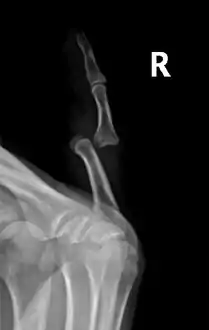

Radiograph of right fifth phalanx bone dislocation